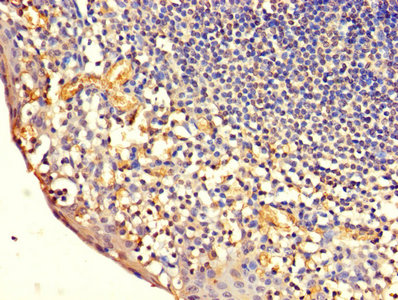

圖片:

應用范圍:ELISA, IHC

Application Recommended Dilution IHC 1:20-1:200 -